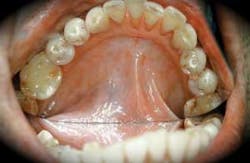

• The second stage of development of submucous fibrosis is characterized by stiff, fibrous bands of tissue that have a white marblelike appearance. See Figure 4. At this stage, there is noted difficulty in the pliability of the tissue and constriction in opening the mouth.